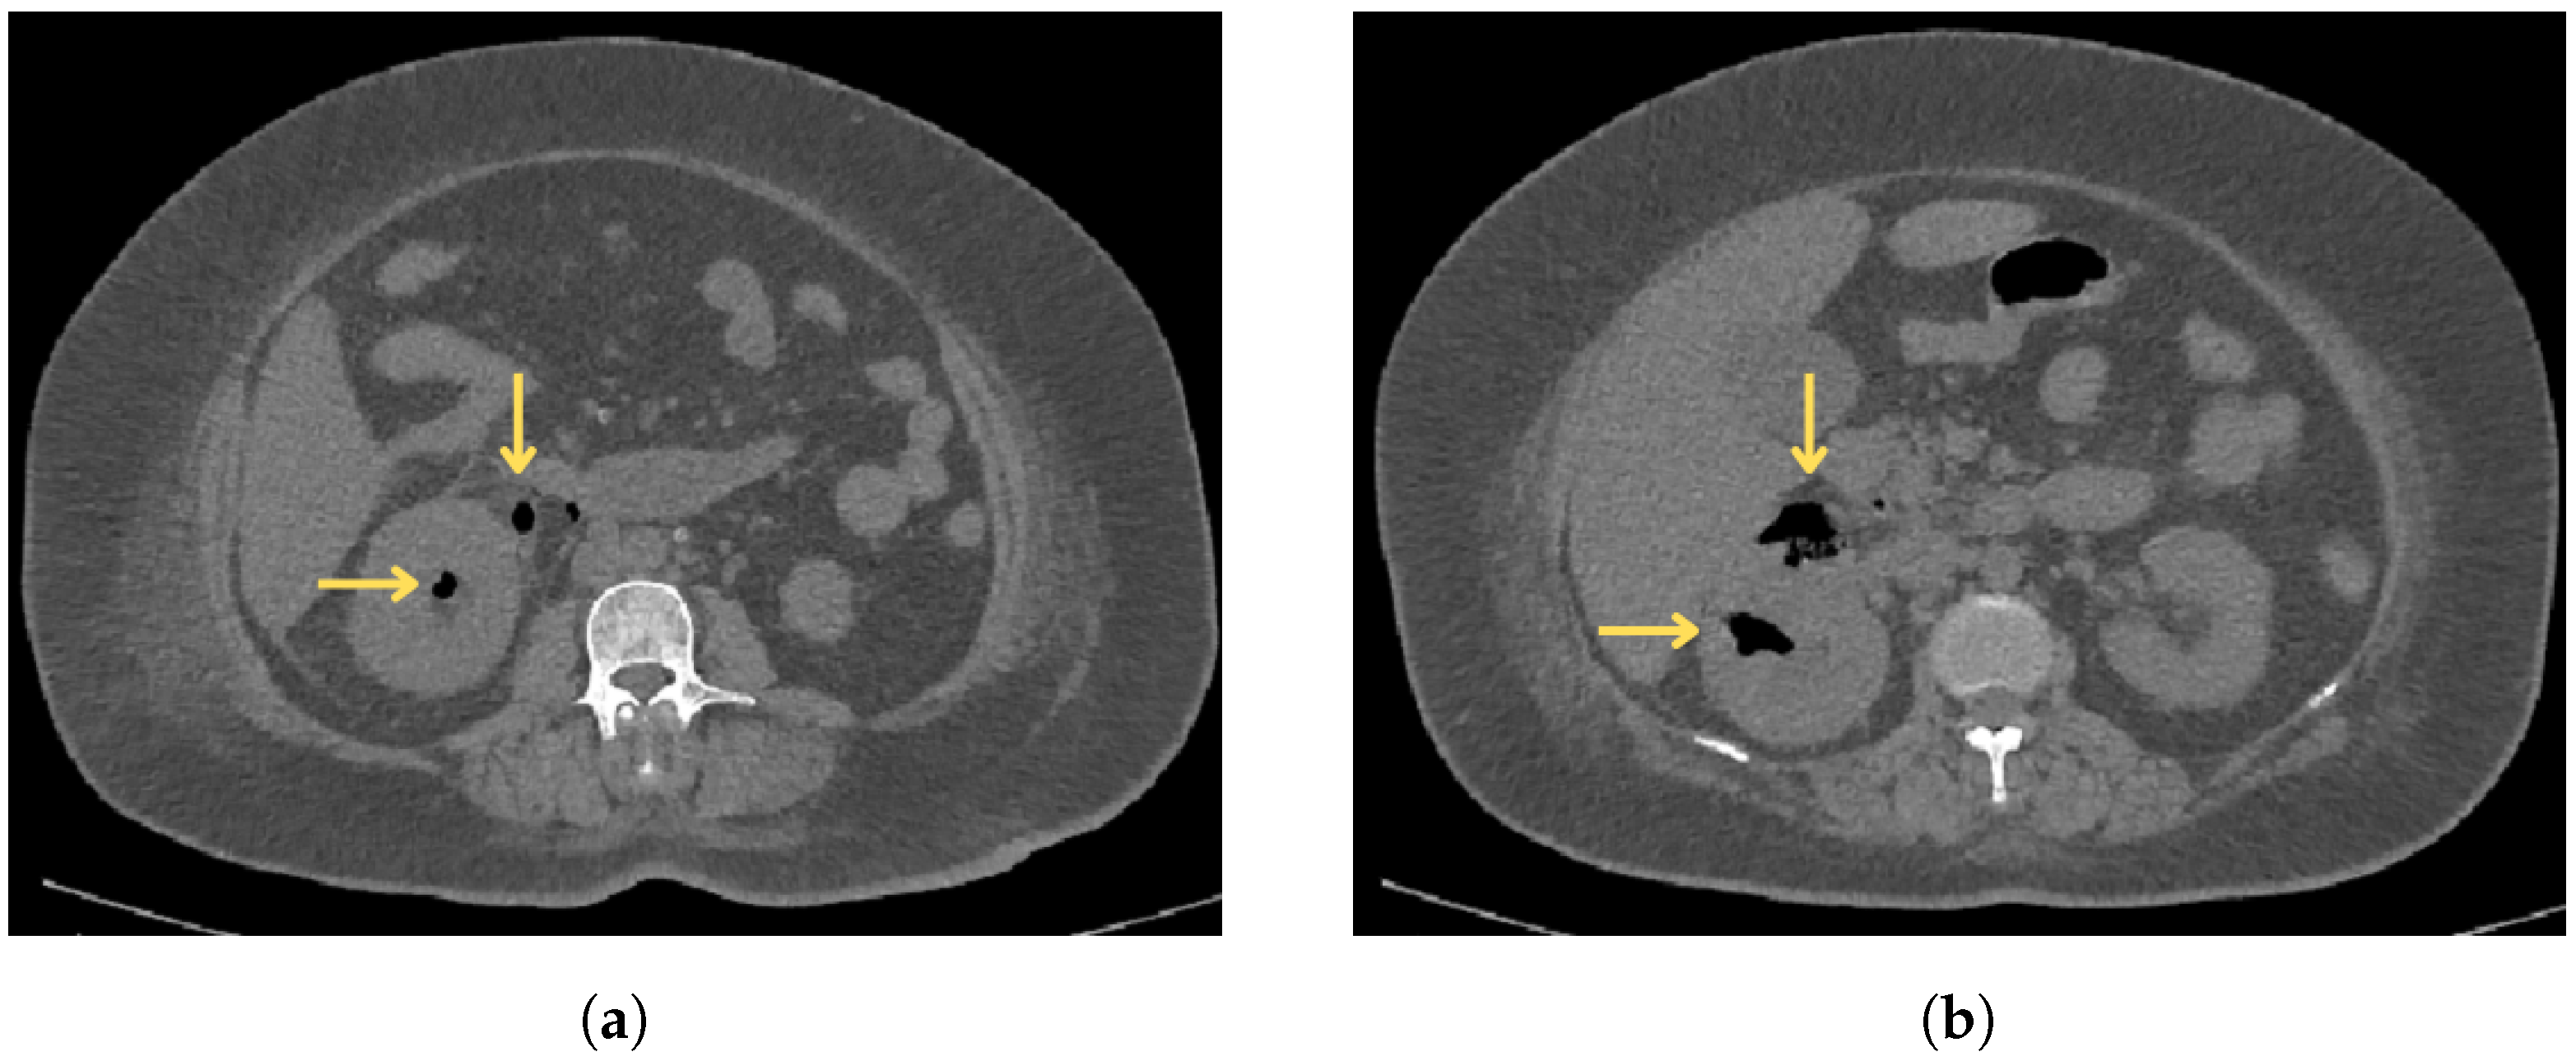

2.3. Diagnostic Findings

| CECT | Contrast-enhanced computed tomography |